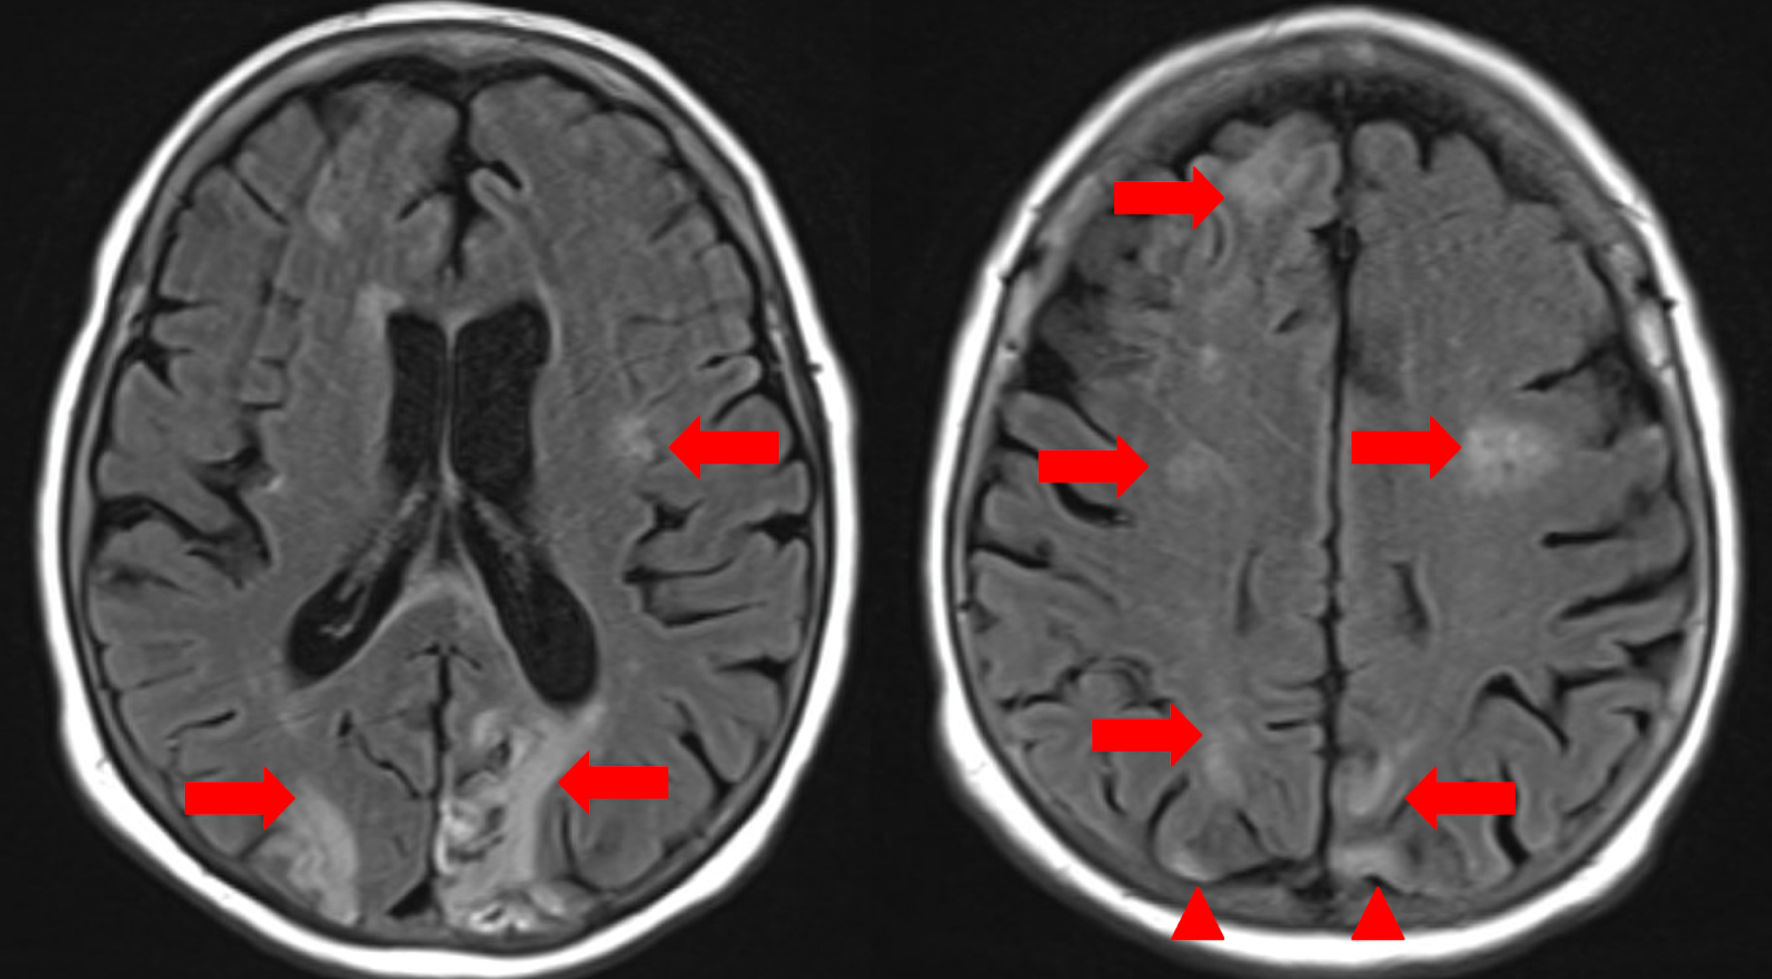

By hospital day 3, follow-up head CT demonstrated extensive right-hemispheric swelling with a progressive midline shift (7 mm to 12 mm), evolving acute ischemia in the posterior and anterolateral right frontal lobes, and diffuse cerebral edema consistent with evolving infarction, without hydrocephalus (Fig. 2). Repeat imaging with dual energy CT showed contrast in the subarachnoid space with no hemorrhage but revealed midline shift (12 mm) with progressive infarction in the right frontal and parietal lobes (Fig. 3). There was no acute hydrocephalus, but there were radiographic signs of increased intracranial pressure (ICP) (Fig. 2). Lumbar puncture was contraindicated by her coagulopathy and imaging findings. Laboratory testing showed hemoglobin 6.7 g/dL (reference 12.0 - 16.0) and hematocrit 21.6% (reference 36.0 - 46.0). Two units of cryoprecipitate were administered and post-transfusion labs showed that hemoglobin had risen to 7.3 g/dL (reference 12.0 - 16.0) and hematocrit to 23.4% (reference 36.0 - 46.0), with persistent thrombocytopenia (platelets 58 × 103/µL, reference 130 - 400) and normocytic indices (MCV 81.5 fL, reference 80.0 - 100.0). Chemistry and coagulation studies demonstrated hyperbilirubinemia (total bilirubin 4.7 mg/dL; indirect bilirubin 3.4), azotemia (blood urea nitrogen (BUN) 62 mg/dL, reference 10 - 25, creatinine 3.50 mg/dL, reference 0.70 - 1.40), and coagulopathy (prothrombin time 26.4 s reference 11.3 - 14.7, INR 2.6 reference 0.9 - 1.2). The patient’s clinical status continued to deteriorate despite maximal supportive measures, including hyperosmolar therapy (mannitol) for cerebral edema and strict blood pressure control to minimize further stroke extension. Broad rheumatologic and infectious workups (antinuclear antibody (ANA), antineutrophil cytoplasmic antibodies (ANCA), rheumatoid factor, anti-cyclic citrullinated peptide antibodies, antiphospholipid antibodies, vasculitis panel, rapid plasma reagin (RPR) for syphilis) were unremarkable. Therapeutic PLEX and methylprednisolone were initiated for TTP as it remained a leading possibility (given thrombocytopenia with microangiopathic hemolysis). Despite maximal supportive measures including ICP-directed therapy, ventilatory management, and PLEX, the patient’s neurological status did not improve. Given the extent of infarction, lack of brainstem reflexes, and poor prognosis, multidisciplinary goals-of-care discussions were held with the family. In light of irreversible neurologic injury and systemic deterioration, the decision was made to transition to comfort-focused care with withdrawal of life-sustaining therapies.

Figure 2. Computed tomography (CT) of the brain (axial non-contrast). Green arrows indicate a worsening leftward midline shift, now measuring approximately 12 mm (previously 7 - 8 mm), due to significant hemispheric mass effect. Yellow arrow highlights hypodensity and swelling in the brainstem and cerebellum, consistent with acute cerebral edema. Red arrow denotes acute subarachnoid hemorrhage within the basal cisterns and right-sided cerebral sulci. Chronic ischemic changes, characterized by volume loss and gliosis in the right occipital lobe and left cerebral hemisphere, would be marked with blue arrowheads for distinction from acute pathology.